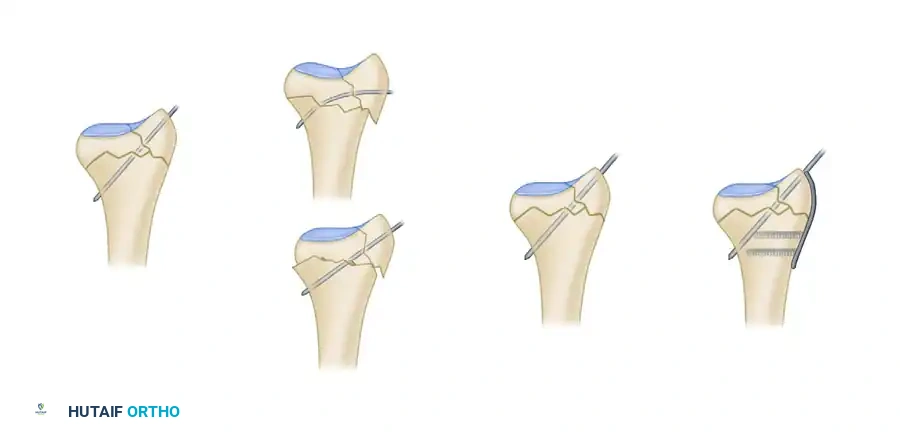

Biomechanics of Pin-Plate Fixation

Traditional radial styloid Kirschner wire fixation provides only a single point of constraint. This single point of fixation acts as a pivot, failing to prevent settling, bending, or radial drift of the distal fragments under physiological loads.

By adding a small buttress plate to the radial styloid pin, the construct is transformed. The pin-plate provides two distinct fixation points: the first through the distal end of the plate, and the second through the intact medial radial cortex. This dual-point constraint prevents collapse, resists dorsal torque, and halts radial migration.

Fragment-Specific Implants and Application

1. The Radial Pin-Plate:

Applied to the radial column, this implant enhances stability by providing a radial buttress. It effectively neutralizes bending forces that would otherwise cause the radial styloid to displace proximally and radially.

2. The Ulnar Pin-Plate:

The dorsal ulnar fragment (often involving the sigmoid notch) is stabilized with an ulnar pin-plate. By proper contouring, this plate can close gaps in the sagittal plane,

Associated Surgical & Radiographic Imaging